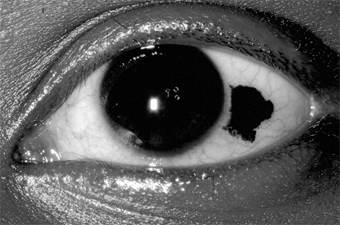

Malignant Melanoma

Malignant melanomas of the conjunctiva are rare. Most arise from areas of primary acquired melanosis; some arise from conjunctival nevi; a few apparently arise de novo from normal conjunctiva. Some are melanotic; others are heavily pigmented (Figure 5-29).

Figure 5-29

Figure 5-29: Conjunctival malignant melanoma.

Many tumors can be locally excised. More radical surgery (eg, exenteration of the orbit) does not usually improve the prognosis. The use of cryotherapy after excision of melanotic tumors may help to prevent recurrences.